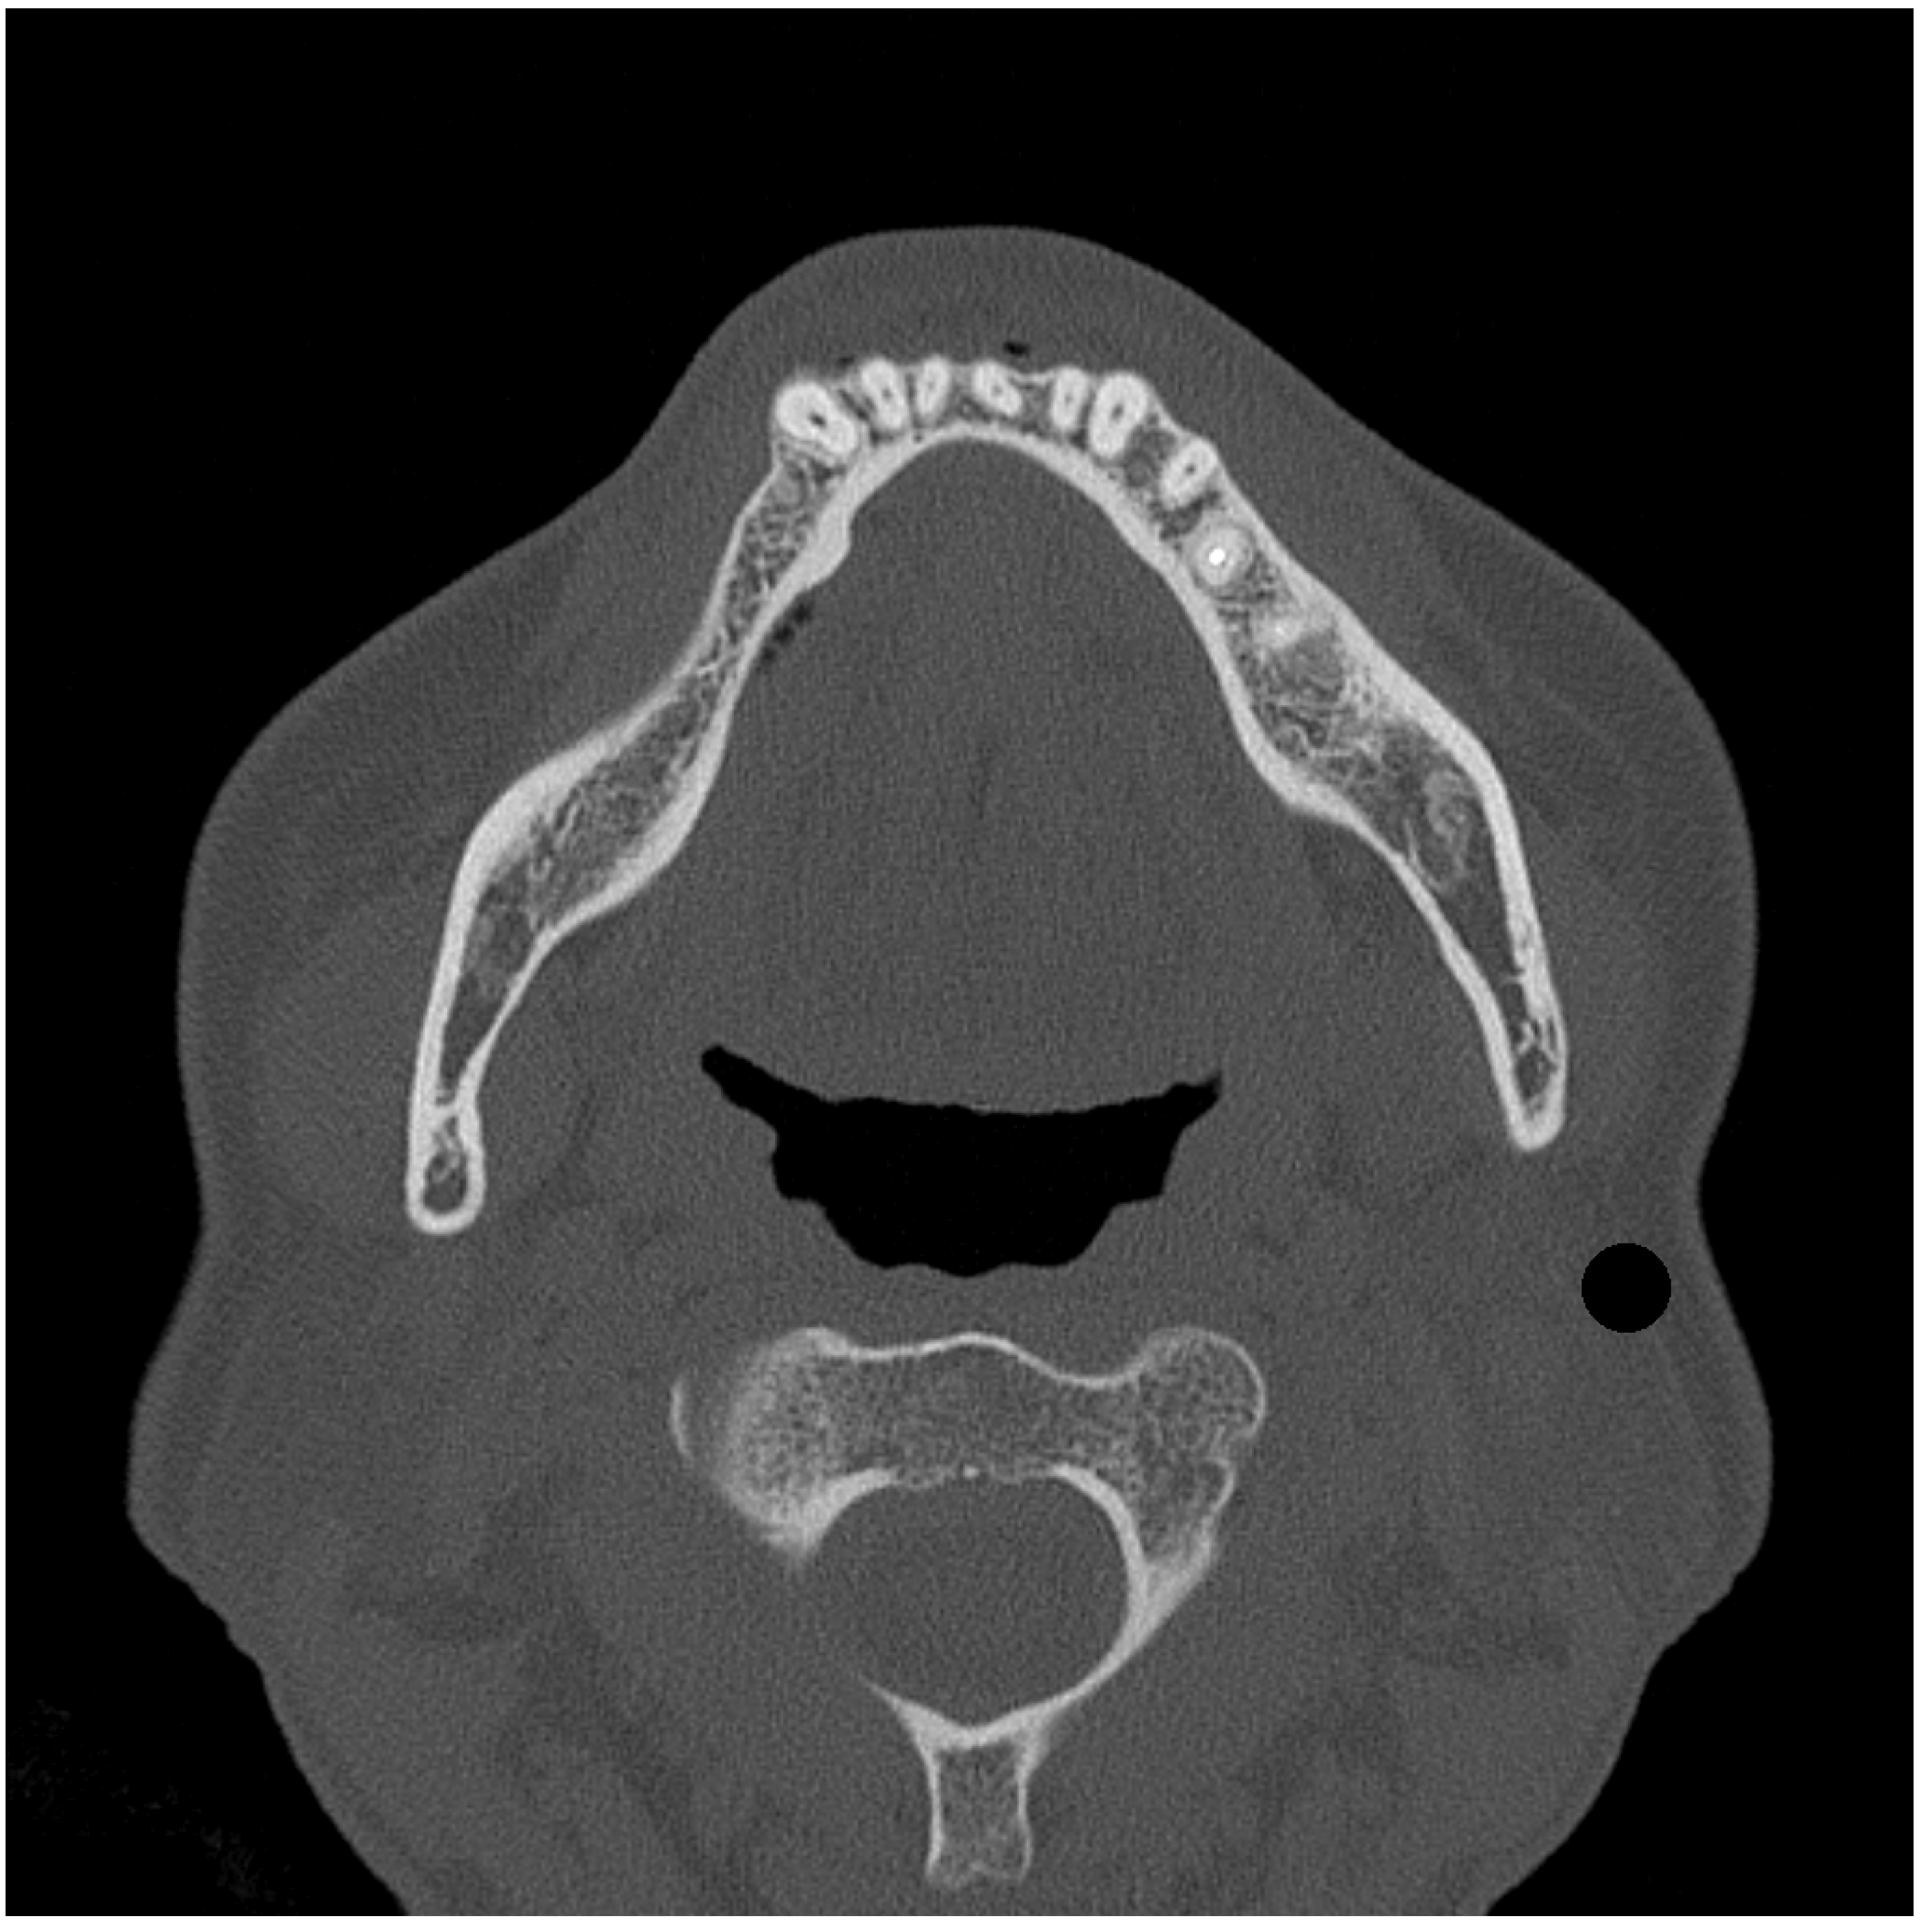

2.1. FE Models